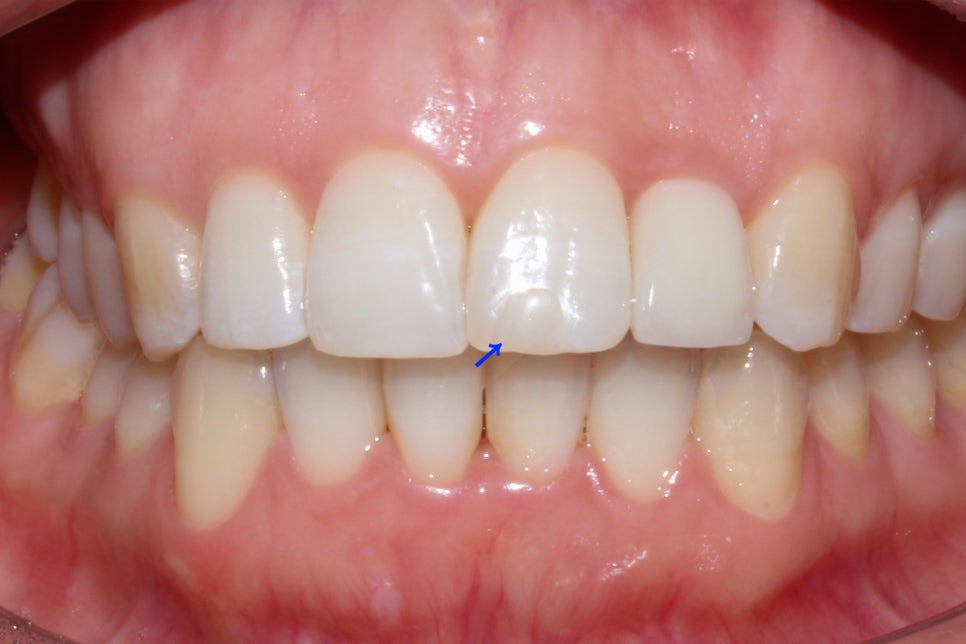

뻐드렁니 교정 전 중절치의 돌출 상태를 보시면

위처럼 중절치가 맹출된 각도가 지나치게

튀어나온 것을 확인할 수 있습니다.

왜소치 외에도 상악 왼쪽 중절치의 표면에

흰 반점이 있는 반상치 증상이 나타나기 때문에

이 부분은 추후 치아색과 비슷한 resin으로

보완하여야 하는데요, 이러한 반상치 증상이

부분적으로 나타나는 것이 아닌 치아 표면에

전체적으로 발생하여 resin 치료가 불가능한 경우

무삭제 라미네이트 '세라필름'을 부착하여

치아의 표면을 매끈하고 균일하게 보완할 수 있습니다.

뻐드렁니 교정 후 중절치의 탈회 부분을 보시면

치아색과 차이가 없는 비슷한 색상의 레진으로

커버된 것을 확인할 수 있는데요,

보다 효과적이고 장기적인 유지를 원하실 경우

레진보다 영구적인 세라필름으로 치아를

수복하시는 것도 좋습니다.